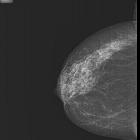

papillary lesions of the breast

Papillary lesions of the breast comprise a wide group and range from benign to malignant.

They develop as tufts of epithelium with a fibrovascular core that arborizes into branching papillae and protrude into the duct lumen.